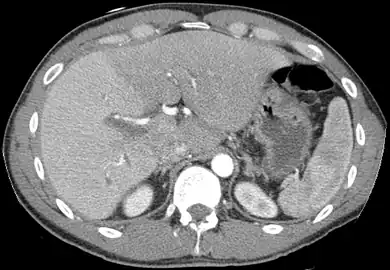

CT scan showing an adult liver in the axial plane

Organogenesis, the development of the organs, takes place from the third to the eighth week during embryogenesis. The origins of the liver lie in both the ventral portion of the foregut endoderm (endoderm being one of the three embryonic germ layers) and the constituents of the adjacent septum transversum mesenchyme. In the human embryo, the hepatic diverticulum is the tube of endoderm that extends out from the foregut into the surrounding mesenchyme. The mesenchyme of septum transversum induces this endoderm to proliferate, to branch, and to form the glandular epithelium of the liver. A portion of the hepatic diverticulum (that region closest to the digestive tube) continues to function as the drainage duct of the liver, and a branch from this duct produces the gallbladder.[35] Besides signals from the septum transversum mesenchyme, fibroblast growth factor from the developing heart also contributes to hepatic competence, along with retinoic acid emanating from the lateral plate mesoderm. The hepatic endodermal cells undergo a morphological transition from columnar to pseudostratified resulting in thickening into the early liver bud. Their expansion forms a population of the bipotential hepatoblasts.[36] Hepatic stellate cells are derived from mesenchyme.[37]